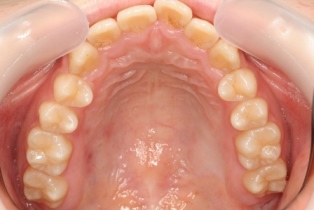

15歳のお姉さんです。治療した歯もなくカリエスフリーです。小学校低学年からメインテナンスしています。病気はありませんが健康維持のため半年に一度メインテナンスに通院しています。虫歯学を元に 科学的に予防できています。結果的に、治療費は安く、痛くなく、治療期間も短く、良いことずくめです。